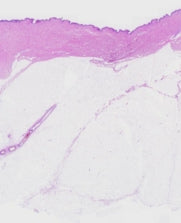

The stimulation of hyaluronic acid slows the oxidation of the skin due to aging, it promotes the absorption of active ingredients and is able to retain up to 1,000 times its weight in water which contributes to good hydration of the skin. skin. The increase in the secretion of adiponectin boosts the synthesis of collagen in the skin to maintain its suppleness. Study conducted in topical application of absolute concentration anti-aging face serum on human skin explants from 10/19/2020 to 03/30/2021. The objective of the study is to assess the benefits of the product on skin biology by measuring the production of compounds in the skin's extracellular matrix, the anti-inflammatory properties as well as the effect on the biology of the hypodermis.